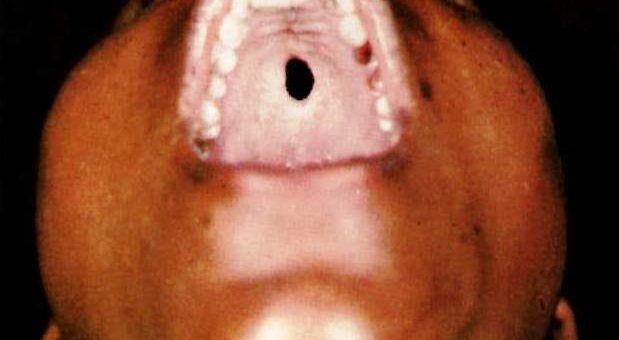

Palate Perforation Not Cleft

I (W. Wertelecki, M.D.) see a palate perforation – not a cleft. Two main possibilities arise, as usual – either this sign is isolated or is associated with other concurrent signs. Open your eyes and it may help to synthesize a hypothesis of cause and diagnosis (see related gallery).

PERSPECTIVE: The two main possibilities are cocaine use or syphilis.